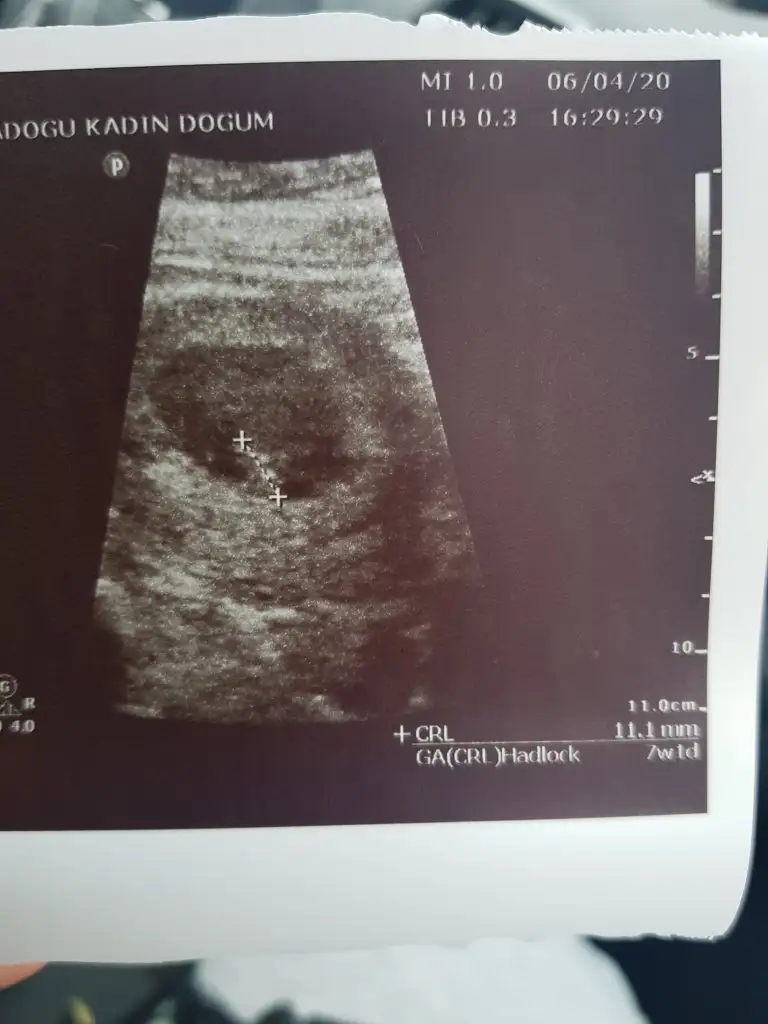

Tesekurler canim5+3 de bebeği ve yolk kesesini gördük canımkalp atışını duymaadık ama bide karından değildi muayne

Canım buda 7 haftalık hali